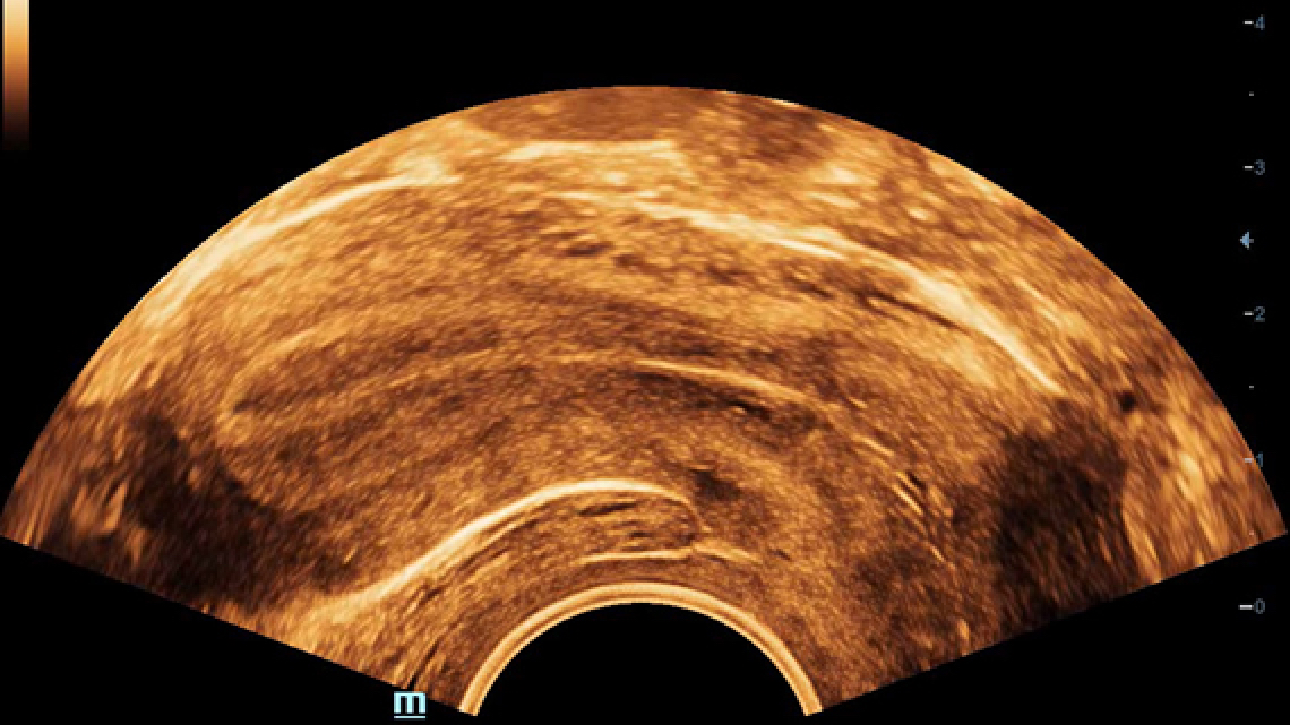

ImĂĄgenes clĂnicas